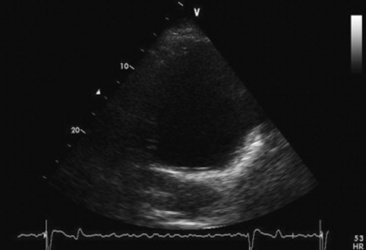

Diagnosis of valvular disease is best performed with a complete echocardiographic examination including M-mode, two-dimensional, and Doppler echocardiography. Two-dimensional echocardiography is superior to M-mode for detection of valvular abnormalities (Figs. 30-8 and 30-9), measurement of valvular masses (Fig. 30-9, B), and the global assessment of ventricular function, but chamber enlargement, high-frequency vibrations of the valve leaflets, and shortening fraction (an indication of ventricular systolic function) can be determined by both. Pulsed wave, continuous wave, and color flow Doppler echocardiography can be used to semiquantitate the severity of valvular regurgitation.92-97 The size of the regurgitant jet detected with pulsed wave or color flow echocardiography is one indicator of the severity of the valvular insufficiency.98 The duration of the mitral regurgitation jet is also important in assessing severity. Clinically insignificant jets of regurgitation are detected only just behind the valve when it is closed. Valvular insufficiency is mild when the jet occupies one third or less of the receiving chamber, moderate when the jet occupies greater than one third but less than two thirds of the receiving chamber, and severe when the jet occupies greater than two thirds of the receiving chamber.

image

Fig. 30-8 Two-dimensional echocardiographic image obtained from the left parasternal window of a ruptured mitral chorda tendineae (arrow) in the left atrium of a gelding with mitral regurgitation and a honking pansystolic murmur.